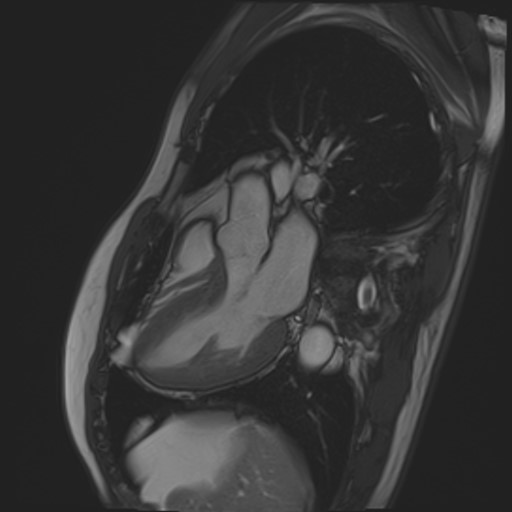

閉塞性肥大型心筋症の心臓に経皮的中隔心筋焼灼術 (PTSMA)を施した画像ですが、MRIでは造影剤を用いる事なく心臓の動きを捉えることができるだけでなく、エタノールにより壊死させた中隔心筋を明瞭に描画することができるので治療効果の判定に有用です。

PTSMA後